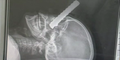

Letzten Freitag stürzte ein 14-jähriger Bursche im Gründstück seiner Eltern in Breitenfurt bei Wien (Bezirk Mödling) mit seinem  Moped. Beim Unfall durchbohrte eine Eisenstange des Zaunes den Unterschenkel des JUgendlichen. Die Rettungskräfte wurden sofort alarmiert.

Die Feuerwehr musste am Unfallort einen Brandschutz aufbauen, weil Benzin aus dem Moped ausgelaufen war. Nachdem der Notarzt den Burschen stabilisiert hatte,  konnte die Feuerwehr mit einer hydraulischen Bergschere die Eisenstange vom Bein trennen.